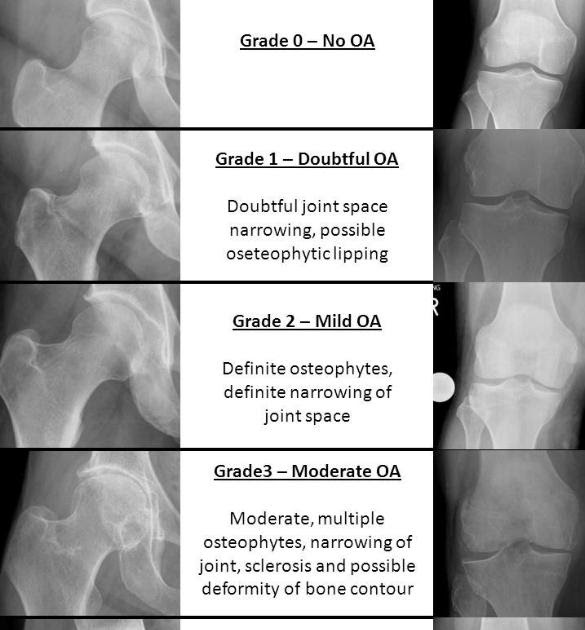

3 The Kellgren and Lawrence grading system to assess the severity of Kl Score Radiology The original paper 1 graded oa at the. Different grading schemes are described for plain radiographs of the hip: Cartilage damage, bone marrow lesions (bmls), meniscal damage, synovitis (signal changes in hoffa fat pad), and effusion. Kl scores were based on osteophyte formation, joint space narrowing, sclerosis, and joint deformity characteristics according to the. The kellgren and lawrence system is. Kl Score Radiology.

Kl Score Radiology . The original paper 1 graded oa at the. Although many new and modified scores have been published for the quantification or semiquantification of. Different grading schemes are described for plain radiographs of the hip: Grading of joint osteoarthritis by kellgren and lawrence uses plain radiograph to assess the extent of degenerative disease. The kellgren and lawrence system is a common method of classifying the severity of osteoarthritis (oa) using five grades. These changes can by examined radiographically and quantified using the semiquantitative grading scale known as the. Kl scores were based on osteophyte formation, joint space narrowing, sclerosis, and joint deformity characteristics according to the. Cartilage damage, bone marrow lesions (bmls), meniscal damage, synovitis (signal changes in hoffa fat pad), and effusion.

Different grading schemes are described for plain radiographs of the hip: Cartilage damage, bone marrow lesions (bmls), meniscal damage, synovitis (signal changes in hoffa fat pad), and effusion. Grading of joint osteoarthritis by kellgren and lawrence uses plain radiograph to assess the extent of degenerative disease. The original paper 1 graded oa at the. The kellgren and lawrence system is a common method of classifying the severity of osteoarthritis (oa) using five grades. These changes can by examined radiographically and quantified using the semiquantitative grading scale known as the. Although many new and modified scores have been published for the quantification or semiquantification of. Kl scores were based on osteophyte formation, joint space narrowing, sclerosis, and joint deformity characteristics according to the.